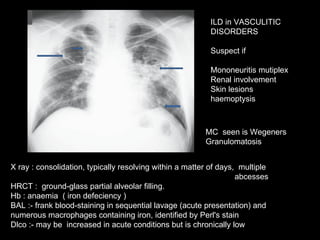

INTERSTITIAL  LUNG  DISEASE  in  VASCULITIC DISORDERS Vasculitic Disorders Lung Involvement ANCA  Interstial Pattern seen Wegener granulomatosis  Common c-ANCA >> p-ANCA 80–90% Diffuse Alveolar Hemorrage with nodules ,cavitation Microscopic polyangiitis Common Common p-ANCA > c-ANCA 80% DAH Churg-Strauss syndrome Common p-ANCA > c-ANCA 30–50% DAH with transient infiltates Goodpasture syndrome Common p-ANCA 10% DAH Takayasu arteritis  Common Negative “

X ray : consolidation, typically resolving within a matter of days,  multiple  abcesses HRCT :  ground-glass partial alveolar filling.  Hb : anaemia  ( iron defeciency ) BAL :-  frank blood-staining in sequential lavage (acute presentation) and numerous macrophages containing iron, identified by Perl's stain Dlco :- may be  increased in acute conditions but is chronically low MC  seen is Wegeners Granulomatosis ILD in VASCULITIC DISORDERS Suspect if  Mononeuritis mutiplex Renal involvement Skin lesions haemoptysis